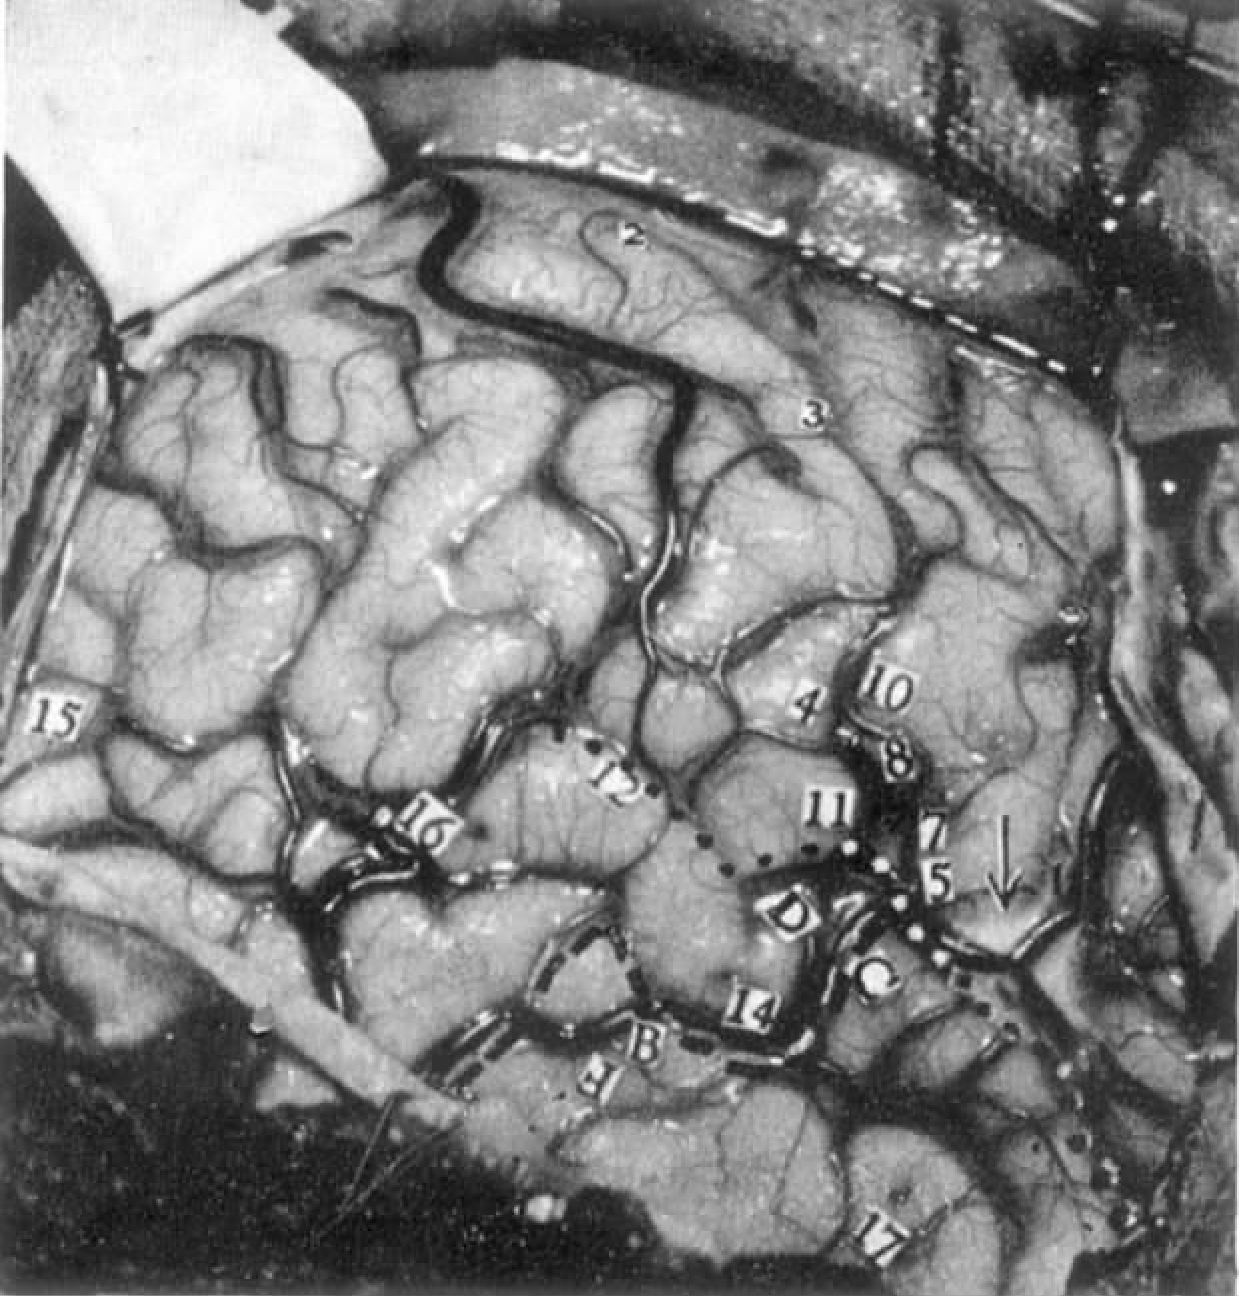

刺激部位

右脑,近中央沟处的运动区及感觉区(见图4-19)。

电刺激脑的反应及特点

刺激条件:频率60Hz,点1到5的电压为1V,之后点的刺激为2V。

11 点1到13标示的是躯体感觉和运动反应的起源位置。令人好奇的是,刺激11点时患者张开了嘴巴,随后还出现打喷嚏和咀嚼运动。

图4-19 病例S.Be.因动静脉畸形,颞叶明显增大(数字所标的为有阳性刺激反应的位置,字母所标的为电活动异常的位置;白色虚线表示要切除的皮质范围)

14 “耳中就像听到某人在私语,或其他什么,有时,听起来又有点像一群人的声音。”给予提醒但未予刺激,他答道:“什么都听不见。”

15 “有人再次试图对我说话,是一个人。”当询问他时,他补充道,“噢,是一个男人的声音,我不能理解他说的什么。”

16 (电极保持原位)患者说,“某些东西带来一些记忆,我能看见七喜瓶装公司和哈里森面包房。”

给予提醒,但未予刺激。他也没糊涂,答道:“什么也没有。”

17 (电极保持原位)“再次听到,但我记不起来了。”问他时,他说那是一个单词,但他记不起来是什么词。

18 (无提醒情况下进行刺激)他说他有点昏昏沉沉的,稍后说:“有人站在我面前,那儿正好坐着一个护士。”

19 (刺激过程中)“我想记起一首歌的名字,还有一台钢琴,某人正在弹奏,你知道,我能听到那歌,那是一首我曾唱过的歌,但我实在想不起它的名字了。”移开电极,当听到以上的记录时,患者补充道:“那正是你们刺激结束后我想做的。”

19 (无提醒情况下重复刺激)在撤除电极后,他说,“某人正在对另外一个人说话,他向我提到一个名字,但我无法理解他的话。”当被问到他是否看到那个人时,他说“那就像一个梦”,当被问到那个人是否在那儿时,他说“是的,先生,就在那个戴眼镜的护士坐的地方。”

19 (无提醒情况下再次重复刺激,同时不问患者问题)“是的‘噢,玛丽,噢,玛丽’某人在唱这个。”当被问到是谁时,他答道,“我不知道,医生,我分辨不出那声音。”

19 (无提醒情况下再次重复刺激)当电极维持原位时,他觉察到“又来了,‘噢,玛丽,噢,玛丽’。”他解释道他曾听过这歌。“它是一首主题曲”,一个收音机节目里曾放过,节目的名字叫做“路易吉的生活”。后来患者与西尔斯医生讨论对那首歌的辨别,最后他唱出了那段著名的歌词“噢,玛丽,噢,玛丽”。当然,所有手术室里的人都听出了这首歌。

21 “某人正在我的左(对侧)耳边说:‘塞尔佛,塞尔佛!’,像我弟弟曾经叫我的声音。”

23 “一个女人在呼叫着什么,但我想不起她的名字。”

24 (用带膜电极进行深部刺激,刺激点指向被掩盖的颞横回。)“嗡嗡声。”

25 (无提醒情况下进行刺激)“我左眼附近有个人。”

25 (无提醒情况下重复刺激)“噢,我的左眼!我看见有人。”稍后他解释道有男人和女人,“他们看起来像在坐着听某人说话,但我看不清那个讲话的人。”

22 恶心感。

19 点19在探测结束前被重复刺激了几次,但刺激没有让他听到那首歌,而且是什么都没听到。刺激电压由2V增加到3V,重复刺激,这导致他觉得恶心,而且吐了,但没有引发任何其他结果。

编者注4

刺激点19的反应值得注意,首先刺激的反应是复杂的。其次,它四次被重复,但隔一段短时间之后,它又不能被重复。